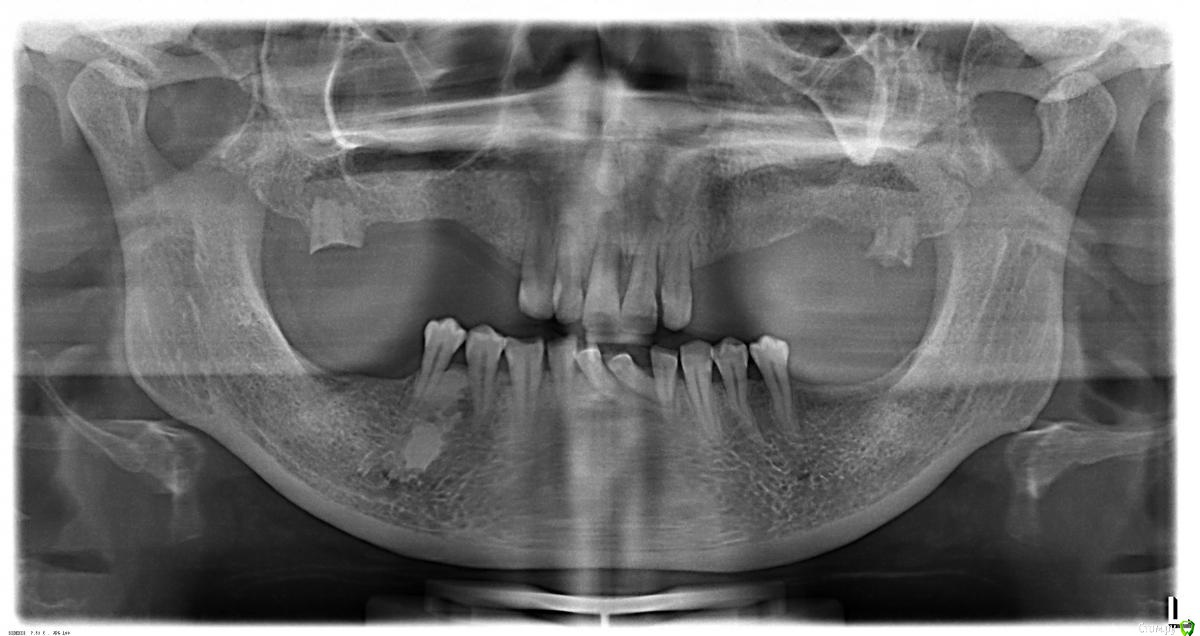

Tatyana_k Опубликовано 1 апреля, 2018 Поделиться Опубликовано 1 апреля, 2018 Пациентка женщина 30 лет нуждается в ортопедическом лечении. На ОПГ определяется рентгеноконтрастное образование на нижней челюсти справа. Уважаемые коллеги выскажите свои соображение по этому поводу. С остальным вроде все понятно. Спасибо заранее. Ссылка на комментарий

krokomot Опубликовано 1 апреля, 2018 Поделиться Опубликовано 1 апреля, 2018 похоже на кортикальную кость нужно кт. Ссылка на комментарий

Astronaft Опубликовано 2 апреля, 2018 Поделиться Опубликовано 2 апреля, 2018 Эностоз, костный островок, компактная остеома. 2 Ссылка на комментарий

masterdent Опубликовано 2 апреля, 2018 Поделиться Опубликовано 2 апреля, 2018 _20180330_5554.jpgПациентка женщина 30 лет нуждается в ортопедическом лечении. На ОПГ определяется рентгеноконтрастное образование на нижней челюсти справа. Уважаемые коллеги выскажите свои соображение по этому поводу. С остальным вроде все понятно. Спасибо заранее. остеома скорее всего. в лечении не нуждается Ссылка на комментарий

Tatyana_k Опубликовано 2 апреля, 2018 Автор Поделиться Опубликовано 2 апреля, 2018 остеома скорее всего. в лечении не нуждаетсяЕсли бы не предстоящее съемное протезирование, вопросов бы не было. В данном случае условия для протезирования и без того неблагоприятные, а тут еще эта типа – остеома? Надо дообследоваться, чтоб потом сюрпризов не было. Спасибо всем за высказанные полезные суждения. С уважением. Ссылка на комментарий

masterdent Опубликовано 2 апреля, 2018 Поделиться Опубликовано 2 апреля, 2018 Если бы не предстоящее съемное протезирование, вопросов бы не было. В данном случае условия для протезирования и без того неблагоприятные, а тут еще эта типа – остеома? Надо дообследоваться, чтоб потом сюрпризов не было. Спасибо всем за высказанные полезные суждения. С уважением. не будет никаких сюрпризов, сделайте кт, посмотрите расположение предполагаемой остеомы-если в губчатом слое - не обращайте внимания, если близко или впритык к компакту - наблюдение в динамике. даже представить не могу каких-либо осложнений съемного протезирования Ссылка на комментарий

Tatyana_k Опубликовано 3 апреля, 2018 Автор Поделиться Опубликовано 3 апреля, 2018 Какая связь съёмника участка остеосклерова???И вообще нафиг съемное в 30 лет???Жалобы пациентки на периодические боли в области этого участка, а также из анамнеза – пациентка вспомнила, что 5-6 лет назад врач обращал внимание на этот участок и речь шла о необходимости маленького хирургического вмешательства, с ее слов, но ничего не делали. Надо выяснить причину дискомфорта. Имплантация дорогое лечение и большинству просто недоступно, поэтому что подешевле. Ссылка на комментарий